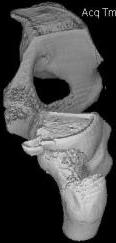

Уважаемые коллеги! Хотелось бы услышать ваше мнение. Мужчина 50л поступил с переломами костей таза. Закрытый перелом крыла подвздошной кости, переднего края вертлужной впадины справа.

Достаточно ли консервативного лечения, стоит ли беспокоиться о переднем крае? В приложении КТ.